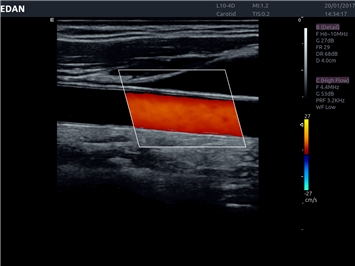

• Повышенная чувствительность при цветовом допплеровском картировании

Цветовой допплер:

Да

IMT (Intima Media thickness):